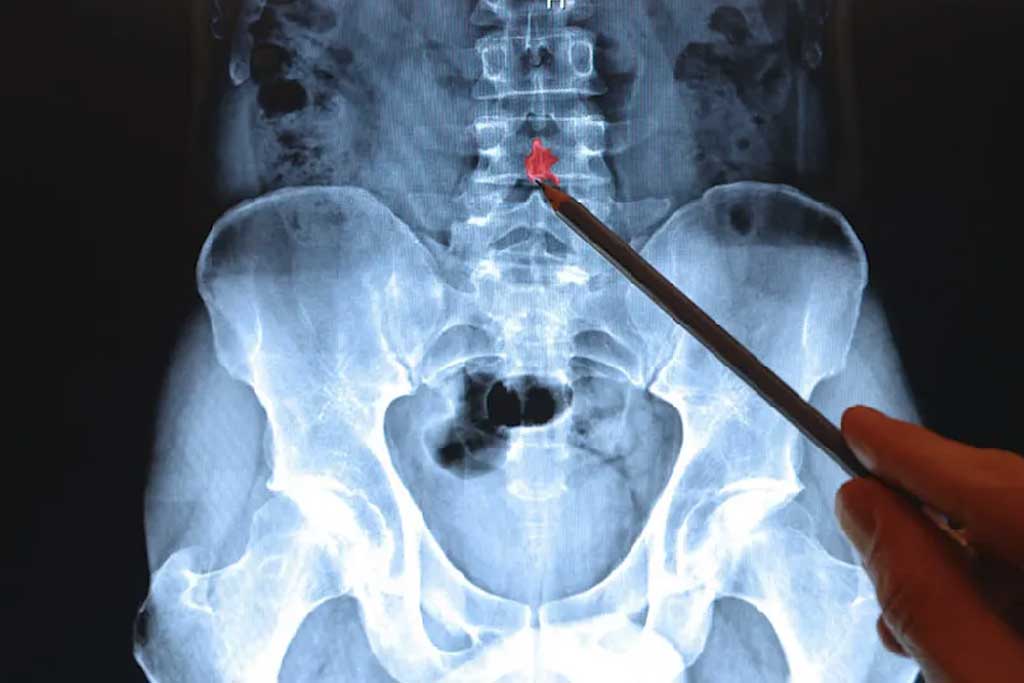

تصویربرداری از ستون فقرات همیشه یکی از بخشهای مهم رادیولوژی تشخیصی بوده است. در بسیاری از بیماران، تصویربرداری یک بخش کوچک (مثلاً یک مهره یا یک بخش کمری) کافی نیست و نیاز داریم کل ستون فقرات را در یک نما بررسی کنیم. اینجا است که رادیوگرافی تمامقد ستون فقرات (Full Spine X-ray یا Total Spine Radiography) وارد میشود.

Full Spine X-ray بهویژه در بررسی ناهنجاریهای اسکلتی مانند اسکولیوز (Scoliosis)، کایفوز (Kyphosis)، لوردوز (Lordosis) و همچنین مشکلات اندام تحتانی نظیر Genu Varum (پای پرانتزی) و Genu Valgum (پای ضربدری) اهمیت دارد.

این روش علاوه بر تشخیص اولیه، برای پیگیری درمان بیماران (ارتوپدی، جراحی، فیزیوتراپی و …) و همچنین برای مستندسازی تغییرات در طول زمان مورد استفاده قرار میگیرد.

اندیکاسیونهای بالینی (Clinical Indications)

در ارتوپدی و اسکلتی:

- تشخیص و پیگیری اسکولیوز (اندازهگیری زاویه Cobb)

- بررسی کایفوز و لوردوز

- بررسی اختلاف طول اندامها و اثر آن بر راستای ستون فقرات

- ارزیابی وضعیت بیماران قبل و بعد از جراحی ارتوپدی (مانند فیکساتورهای ستون فقرات یا زانو)